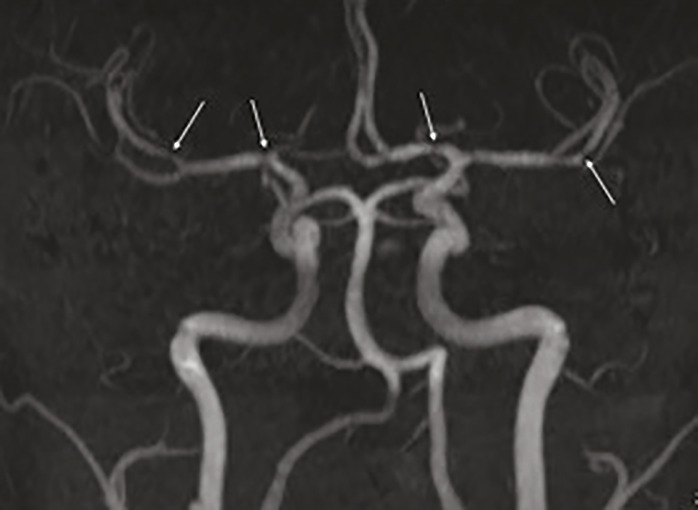

Le patient bénéficie d’un traitement oral par nimodipine pendant quatre semaines. L’évolution est favorable, avec disparition de la symptomatologie et des anomalies vasculaires sur l’imagerie réalisée à six semaines (fig. 2).

Dans le SVCR, l’imagerie cérébrale avec acquisition angiographique initiale peut être normale et doit donc être répétée. L’aspect radiologique typique est une alternance de vasoconstrictions et de dilatations artérielles segmentaires et diffuses en « collier de perles ».